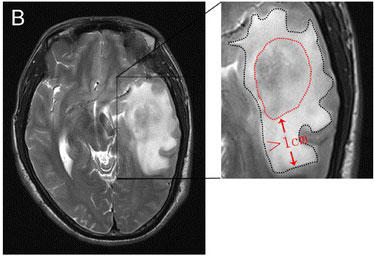

An MRI image of a brain tumor and swelling in the area around it.

An MRI image of a brain tumor with major swelling around it.

Credit: World J Surg Onc. March 2015. doi: 10.1186/s12957-015-0496-7. CC BY 4.0.

The use of steroids to manage symptoms of brain tumors, such as the buildup of fluid in the brain, may limit the effectiveness of immunotherapy drugs against these tumors, a new study suggests.